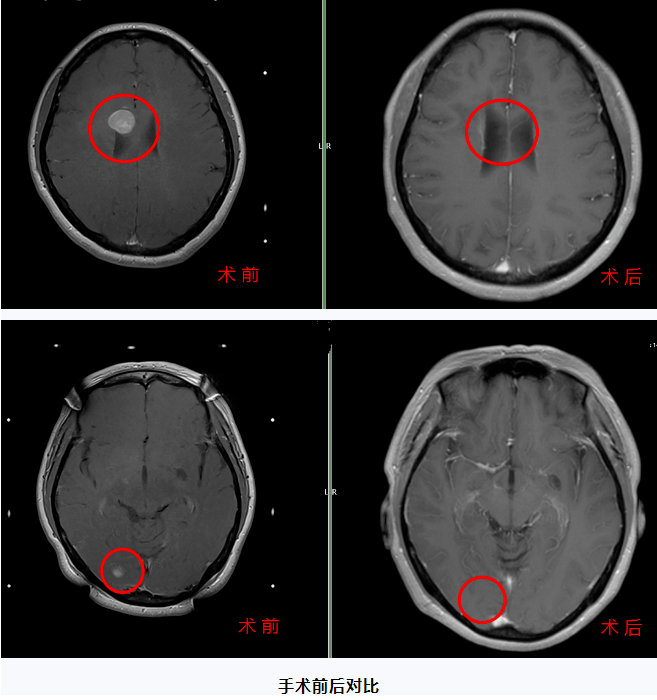

临床病例

患者陈女士(化名)经颅脑CT及PET-CT检查提示颅内占位,之后进行立体定向脑活检术被确诊为“淋巴瘤”,放化疗后病情趋于稳定。2021年底肿瘤复发。2021年12月28日到首都医科大学三博脑科医院福建院区(福建三博福能脑科医院)伽马刀中心治疗,两天后顺利出院。2022年陈女士来院复查MRI,医生发现原有的淋巴瘤消失了!